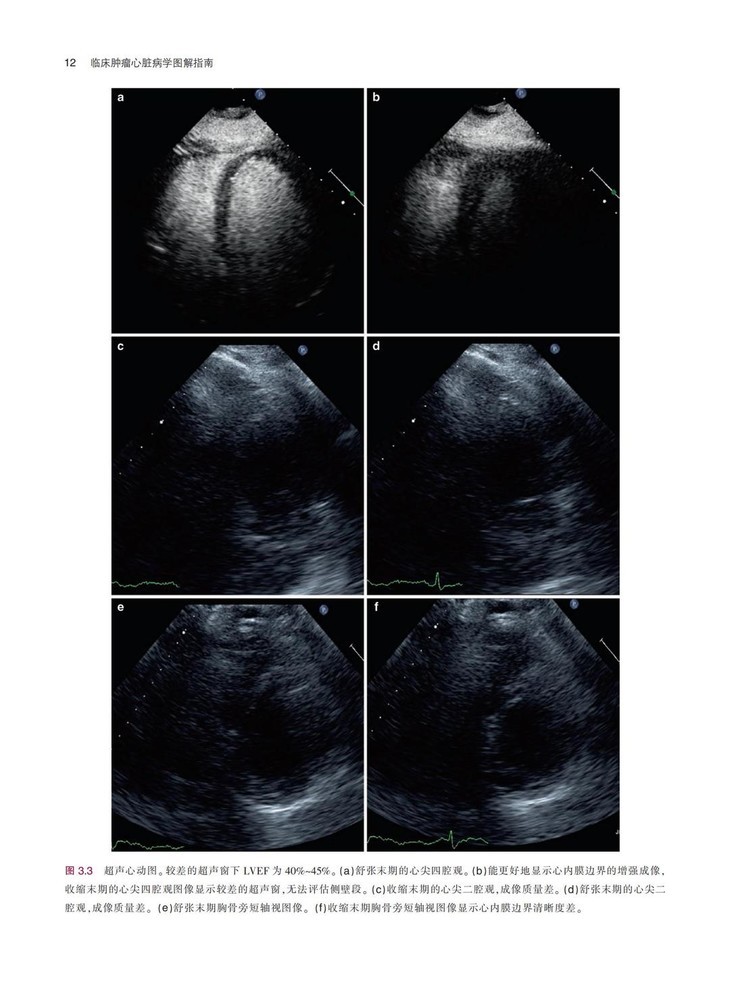

《临床肿瘤心脏病学图解指南》一书结合丰富的临床病例,系统地描述了癌症与心血管领域常见的临床问题,患者主要为既往有心血管疾病的癌症患者,或癌症患者继发复杂心血管疾病,全书对疾病的诊断、检查方式、治疗方式等内容进行了详细阐述,并配有大量的图片,可帮助读者更加清晰地了解相关内容。本书通过结合相关临床病例的方式,在强化理论的同时,突出临床应用特性。本书对我国临床肿瘤心脏病学的基础研究和临床实践有明确的指导意义,对于肿瘤或心血管领域的临床医师及相关研究者具有很强的参考价值。

配有大量手术图片和超声图片,图文并茂,可以为读者提供临床指导,实用性很强